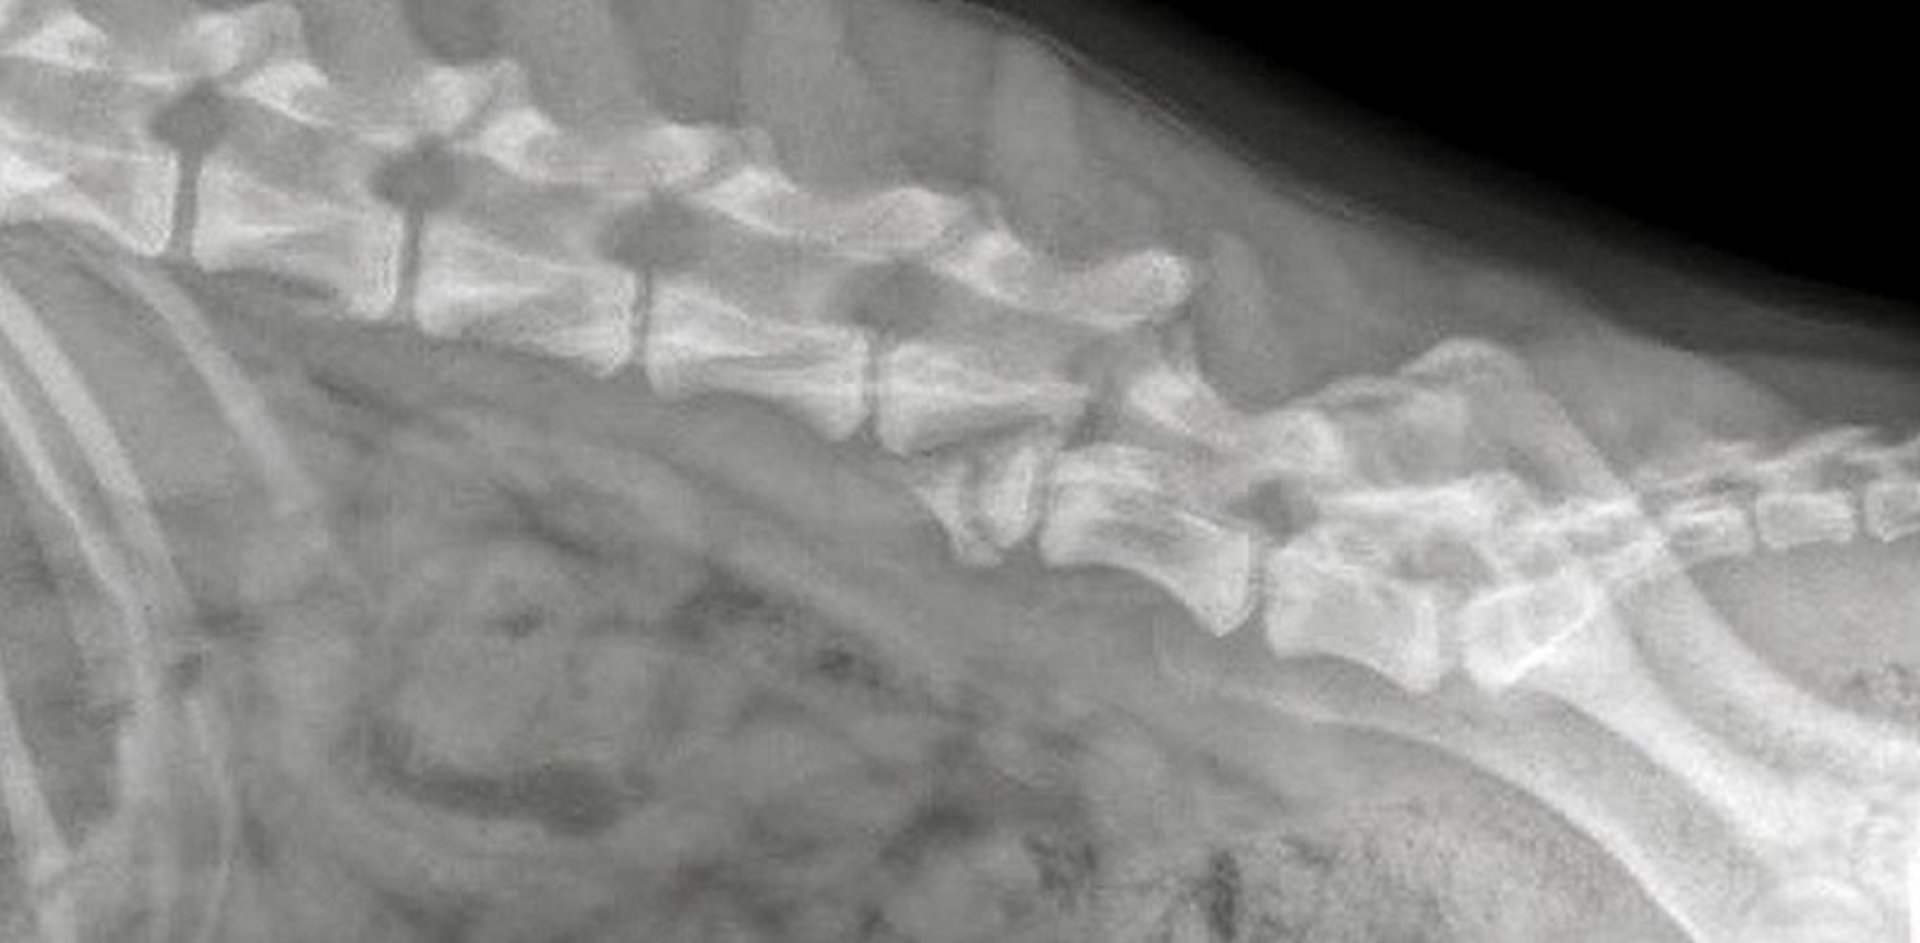

Clinical signs of spinal trauma are typically acute and may progress in instances of unstable fractures or luxations. Severe thoracolumbar spinal cord injury may cause paraplegia with increased extensor tone in the thoracic limbs (Schiff-Sherrington phenomenon). Radiographs usually demonstrate vertebral fractures and luxations. However, in dogs with trauma, radiographs, compared with CT, reveal only ~75% of spinal fractures; therefore, advanced imaging is indicated in animals with suspected spinal trauma and normal radiographs. Animals with mild neurologic deficits often recover with 4–6 weeks of cage or stall rest and analgesics. Surgical reduction and stabilization is indicated for unstable vertebral injuries causing severe neurologic dysfunction. The prognosis is guarded for recumbent horses and cattle. In animals that have lost deep pain perception caudal to the lesion, the prognosis for return of neurologic function is poor.